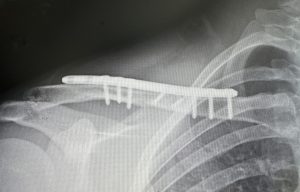

As the clavicles can be shortened for shoulder narrowing they can also be expanded or lengthened by a similar osteotomy location. A sagittal split osteotomy can be done at the mid-shaft of the clavicle which allows the bone to be lengthened while a central full-thickness contact of the bone is maintained. In this method partial thickness horizontal back cuts are made in the bone connected by a full-thickness vertical or sagittal cut between them. The outer clavicle segment is then slide out to the desired amount of lengthening, or the amount of lengthening the shoulder tissues will permit to occur, and the two overlapping central segments screwed together. A long superior clavicle plate is then applied with three screws on each uncut full thickness clavicle segment. The partial thickness bone gaps are filled in by the application of tissue back precision cut fibular bone grafts.

The sagittal split osteotomy method should provide good healing of the central full thickness overlapping bone segments provided the plate and screw fixation remains stable. In the partial thickness defects created by the lengthened sagittal split of the bone healing is promoted by the use of solid bone grafts. I find now that this is superior to the previous use of bone putty.

The limits of the amount of clavicle lengthening that can be achieved is controlled by two factors, the geometry of the sagittal bone cut but, more importantly, the restrictions of the shoulder tissues to be pushed outward. The soft tissue attachments to the humerus and scapula have a blocking effect on the shoulder joint moving laterally. Most patients should be able to achieve 15mms per side with the maximum amount being 20mms per side. (the limits of the ability of the superior plate application which must be done outside of the split bone area)